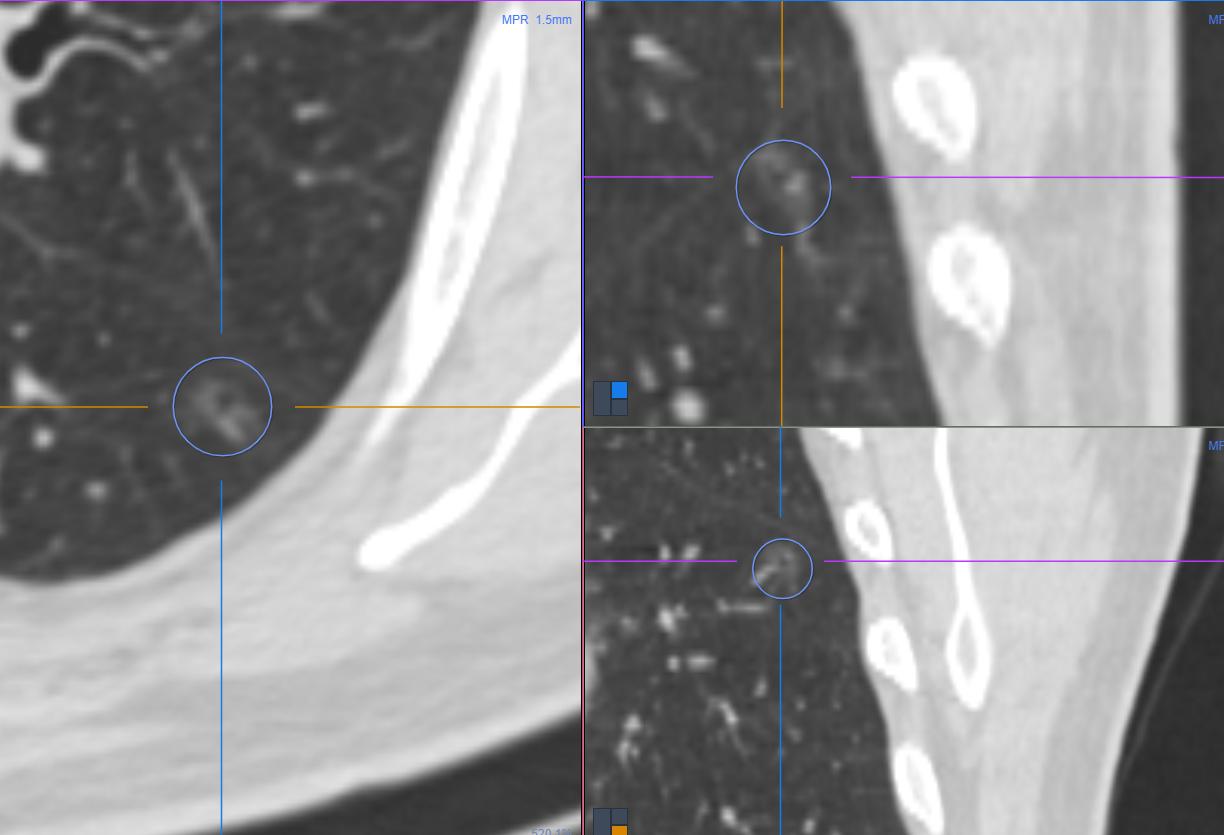

结节一:

直接看最早和现在的比较:

结节横断面形态

数值比较

很显然是一个空泡型肺结节,空泡结构完整,结节壁厚薄不均,相邻斜裂胸膜增厚,间隔15个月两次比较病灶体积、面积和治疗均轻度增大,CT值略增高。首先间隔15个月,该病灶首先排除为炎性病变,第二个病灶形态欠规则,结节壁厚度略有增加。两次略有变化,此类结节,大部分即使观察短期内暂时无风险,经过和老乡的沟通,此类结节有浸润的一些征象。通过语音沟通,患者也感觉到具有潜在的风险,早晚都需要处理,患者自己也觉得有必要性,毅然决定手术治疗。